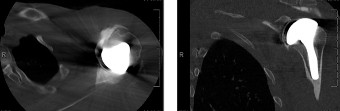

A 22-year-old male with a history of multiple shoulder dislocations was treated with an arthroscopic Bankart repair 9 months ago. Over the last 3 months, he has tried returning to sports but reports continued anterior subluxation events. Revision surgery has been recommended, and he comes to you for a second opinion. His CT

scan is shown above (Fig. 2–36).

Figure 2–36

The correct answer is (B). In patients who have undergone a capsulolabral repair for instability and continue to be symptomatic, it is important to carefully assess the degree of glenoid bone loss. This is best done with a 3D CT scan. When viewing sagittal images, the inferior two-thirds of the glenoid should be a perfect circle. Bony defects can be appreciated by loss of this circle with bone missing from the 230 to 430 position. This may result in the glenoid taking on the classic inverted pear-shaped configuration that is associated with recurrent anterior instability (see Fig. 2–37). The average circle diameter is 24 mm and the average bone loss associated with a pear-shaped glenoid is 35% or 7.5 mm off the anterior rim. The critical amount of bone loss that destabilizes the shoulder is between 15% and 25% hence bone loss at or above this level must be treated with a bony procedure rather than capsulolabral repair.